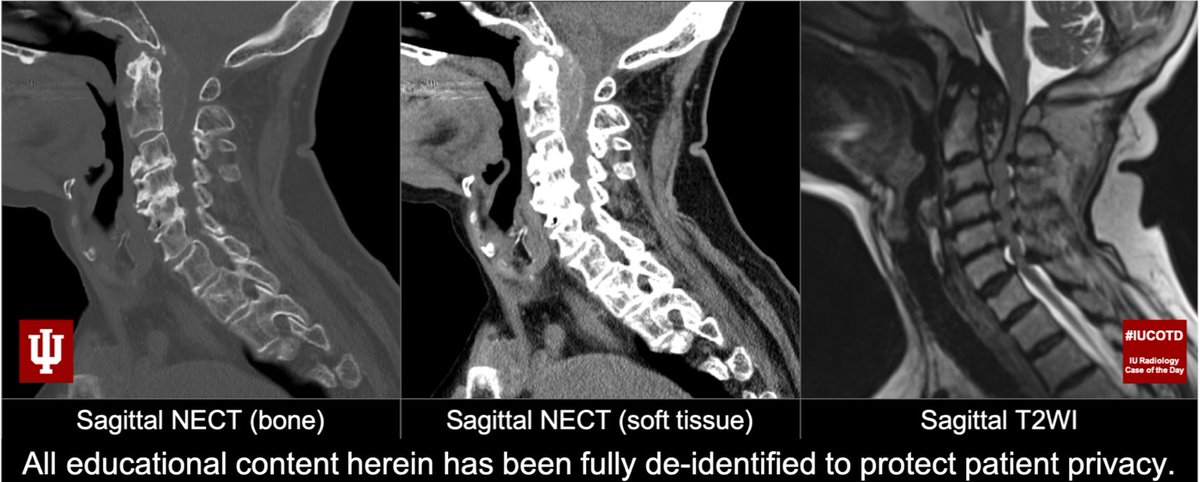

#IUCOTD #188: Chronic neck pain. Findings? Differential diagnosis? Top Diagnosis?#FOAMrad#MedEd#NeuroRad#SpineRad#Radiology#FOAMed Answer w/ appropriate GIF ONLY -- stay professional & don't spoil the answer!@IURadiology#IUCOTD#YouTube: https://bit.ly/2EXkWnX pic.twitter.com/SC67bciCI3

#IUCOTD #175 ANSWER: C-spine rheumatoid arthritis!#FOAMrad#MedEd#RadRes#NeuroRad#SpineRad Learn more: https://youtu.be/aosrexGM_xo@IURadiology#COTD site: https://radtf.iuhealth.org/cotd#IUCOTD#YouTube: https://bit.ly/2EXkWnX No#IUCOTD next week d/t US Independence Day holiday! pic.twitter.com/daDzbE6p71